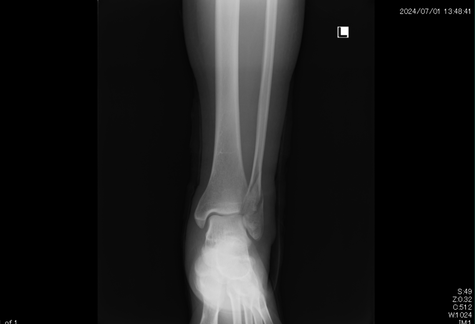

●左腓骨遠位端骨折

足首を捻り外側の骨 足首に近いところを骨折をしてしまいました。整形外科での診断後 手術の予定が決まりそれまでの間シーネ固定することになりましたが、手術療法に不安があり保存療法(自然療法)をインターネットで検索中当院のホームページにたどりつきました。

結果的に2時間以上かけて当院に来院。保存療法で治療することになりました。コンパクトな固定ギプスと患部の血行を促進 超音波治療により腫れも痛みも軽減。経過良好でした。

4か月後には予定していた巡礼の旅 50kmの道を完歩することができました。なによりも手術の痕を残さず自然療法で完治したことに喜んでもらえました。